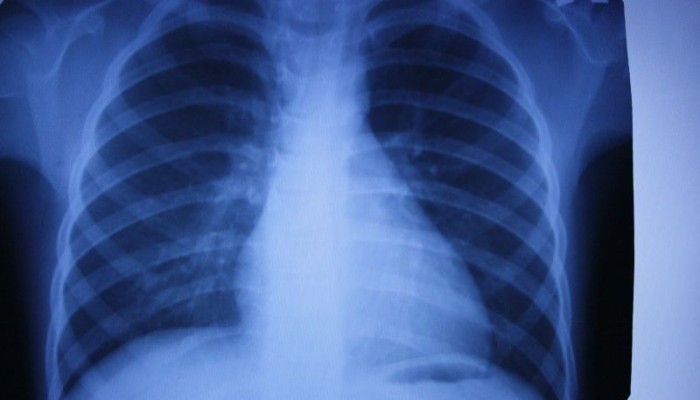

Сердце

Этот орган является достаточно плотным по структуре, плюс содержит внутри своих полостей кровь. Такое строение обусловливает непроницаемость его для рентгеновского излучения, что создает в центре снимка массивное светлое пятно. Изменение его формы может наблюдаться при следующих заболеваниях:

- При гипертонической болезни со временем происходит увеличение левого желудочка сердца, что проявляется значительным расширением тени сердца кнаружи.

- Различные пороки клапанов также являются причиной изменения нормального положения сердца на снимке. Увеличение тени происходит как в области предсердий, так и желудочков, что позволяет даже по рентгену предположить диагноз.

- Образование аневризмы – расширение стенки сосуда – нередко происходит в области начальных отделов аорты. Её развитие будет сопровождаться увеличением ширины тени сосудистого пучка, или появлением в его области округлого выпячивания.

Изменения тени сердца на снимках редко позволяет сразу же установить диагноз, но позволяет заподозрить его, и отправить пациента на более информативное обследование.